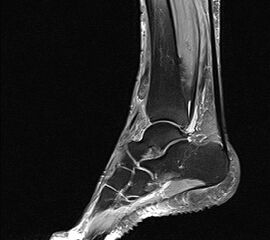

Bildgebende Diagnostik bei der Ruptur des MTA mittel MRT:

Sagitaler Schnitt  mit Darstellung des nach proximal retrahierten Stumpfes der rupturierten Sehne.

Abbildung 2

Der Gold-Standard zur Diagnostik einer ansatznahen Tendopathie des M. tibialis anterior ist die Magnetresonanz-Tomographie (Abbildung 2).

Hierbei können zum Beispiel  peritendinöse Flüssigkeitsansammlungen auf Höhe des Sehnenansatzes bzw. der distalen Anteile der Sehne darstellt werden. In Einzelfällen können Längsrupturen als Zeichen einer chronischen Schädigung nachgewiesen werden. Einschränkend ist zur Beurteilung der M. tibialis anterior-Sehne im MRT der anatomische Verlauf anzusehen. Schädigungen, insbesondere Längsrupturen, können aufgrund des Verlaufs außerhalb der MRT-Schichten leicht übersehen werden. Daher sollte die gesamte Sehne entsprechend ihres Verlaufes mittels Adaptation der Schnitteben erfasst werden. Das MRT stellt den Gold-Standard zur Diagnostik einer Ruptur der M. tibialis anterior-Sehne 1920 dar.

In der Regel tritt die Ruptur 0,5 bis 3 cm proximal der Insertion auf. Dieses Areal entspricht der anatomisch bekannten avaskulären Zone. Die Ruptur kann in der Regel auf den sagittalen und axialen Schnittbildern identifiziert werden. Bei Vorliegen des Verdachts auf eine M. tibialis anterior Sehnenruptur ist jedoch das zusätzliche Anfertigen schräg-axialer Flächen sinnvoll. Dabei sollte die schräg-axiale Schnittebene senkrecht zum Verlauf der M. tibialis anterior Sehne auf Höhe des anterioren Talus liegen mit einem Winkel von 45° zwischen der axialen und koronaren Fläche. Hierbei lassen sich insbesondere komplette Rupturen von partiellen Rupturen unterscheiden 21. Hinsichtlich der Gewichtung zeigen sich die Rupturen auf der T1-Schichtung mit Fettsättigung als auch auf der T2-Sequenz sehr gut. Meist lässt sich die Ruptur mit einem retrahierten Stumpf darstellen. Zusätzlich kann eine umgebende Signalerhöhung mit Erguss den Sehnenstumpf markieren (Abbildung 2).